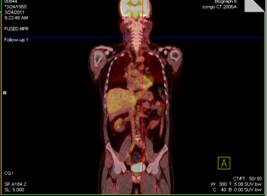

• Chụp PET/CT đánh giá toàn thân trước điều trị: Hình ảnh khối hạch vùng cổ trái kích thước 10x12 cm, tăng hấp thu FDG mạnh. Cơ quan bộ phận khác không thấy tăng hấp thu FDG.

• Hình 1: Hình ảnh khối hạch vùng cổ trái kích thước 10x12 cm, tăng hấp thu FDG mạnh (vòng tròn vàng).